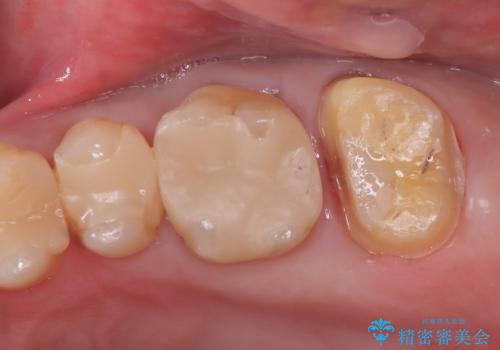

- 患者様は、左上7のメタルインレー(銀の詰め物)の見た目が気になるとのことで来院されました。診察したところ、メタルインレーの下にむし歯の再発リスクがあることも確認。より審美性と耐久性を高めるため、メタルインレーを除去し、セラミッククラウンで補綴する治療計画を立てました。

メタルインレーを丁寧に除去し、歯の状態を確認。その後、精密な形成を行い、適合性の高いセラミッククラウンを装着しました。セラミッククラウンは天然歯に近い見た目で、美しさだけでなく強度や機能性にも優れているため、患者様にも「自然な仕上がりで違和感なく噛める」と大変ご満足いただきました。